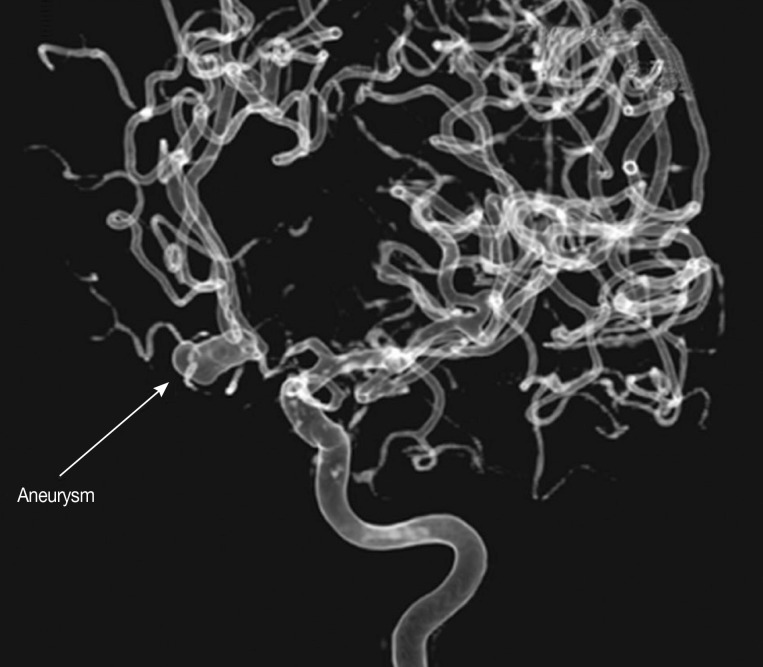

The inclusion criteria included non-traumatic SAH patients for whom 1) results of CT brain imaging (

Fig. 1) or MR imaging of the brain were available, 2) results of CT angiography (CTA) or MR angiography (MRA) or 3-dimensional digital subtraction cerebral angiography (DSA) were available (

Fig. 2) to identify any intracranial aneurysm that might be present (

Fig. 2Three-dimensional digital subtraction cerebral angiography (DSA) showing the normal posterior circulation artery, vertebral artery, basilar artery, posterior cerebral artery, and superior cerebellar artery.